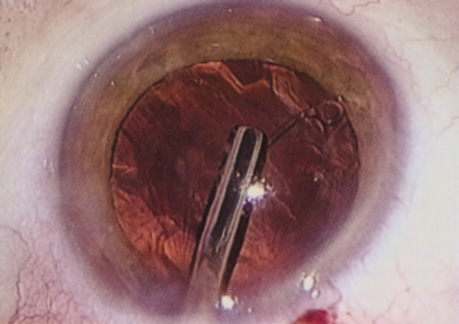

HYDRODISSECTION

Hydrodissection can be performed after the surgeon has successfully completed capsulorrhexis.97 If the capsulorrhexis is not intact, fluid forced around the interior of the capsule may cause the bag to splay open. With capsulorrhexis, hydrodissection is a safe and extremely useful maneuver. Hydrodissection can be thought of as two maneuvers: hydrodelineation and cortical cleaving hydrodissection. By placing a 27-gauge cannula on a syringe filled with balanced saline solution (BSS), the surgeon can direct fluid beneath the residual anterior capsular rim to create a cleavage plane. Depending on the direction the fluid wave takes, different lamellae of the cataract will be separated. Hydrodelineation is the term used when the cleavage plane separates the adult nucleus from the fetal nucleus or the adult nucleus from the more peripheral epinucleus. Hydrodelineation often results in the characteristic golden ring sign (Fig. 11). Cortical cleavage occurs when the cortex is separated from the capsular bag (Fig. 12). Finding the cortical cleavage plane may be facilitated by gently lifting the capsular margin away from the cortex with the BSS cannula before injecting. Several small bursts of fluid allow the surgeon to monitor progress of the fluid wave. When dealing with a soft nucleus, the authors strive to perform true cortical cleaving hydrodissection. For a hard nucleus, hydrodelineation allows manipulation of less of the nuclear bulk, although the remaining epinuclear shell must be addressed in an additional step. Hydrodelineation is particularly useful if the nucleus is not freely mobile after cortical cleaving hydrodissection.

Fig. 11. A crisp “golden ring” is seen from the fluid cleft between the epinucleus and nucleus with hydrodelineation.

Fig. 12. Hydrodissection, performed subincisionally with a 27-gauge J-cannula, produces a cleavage plane between the capsule and the cortex. The small blue arrows indicate the advancing fluid wave.